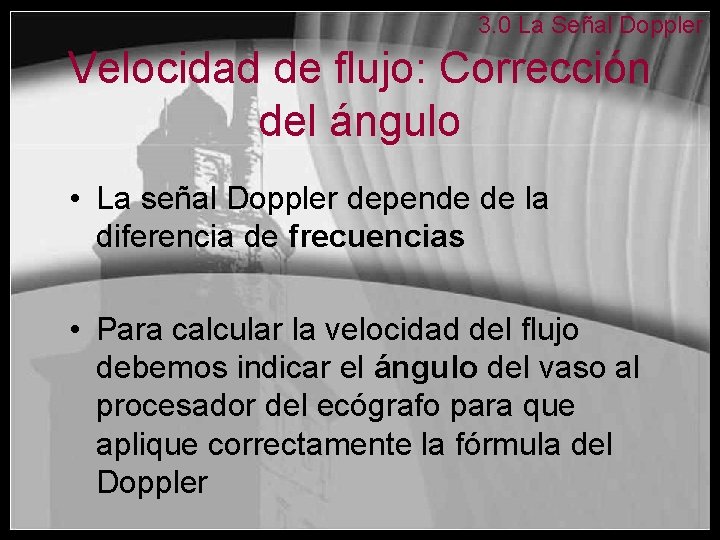

3. 0 La Señal Doppler Velocidad de flujo: Corrección del ángulo • La señal Doppler depende de la diferencia de frecuencias • Para calcular la velocidad del flujo debemos indicar el ángulo del vaso al procesador del ecógrafo para que aplique correctamente la fórmula del Doppler